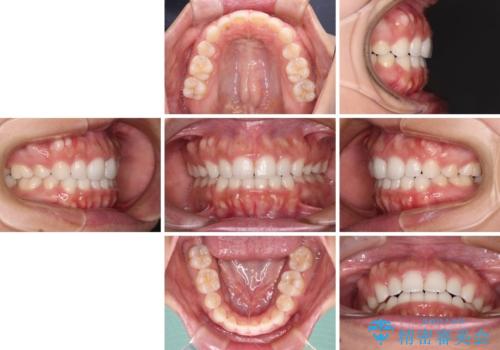

目立たない装置で横顔のシルエットを改善 ハーフリンガルでの抜歯矯正

- 口元の突出感を気にして来院された患者様です。

上下左右の第一小臼歯4本を抜歯して口元を下げる治療計画としました。

表側のワイヤー矯正に比べると治療期間は長く、費用も高額となりますが、どうしても目立たせたくないという方にはお勧めの抜歯矯正です。